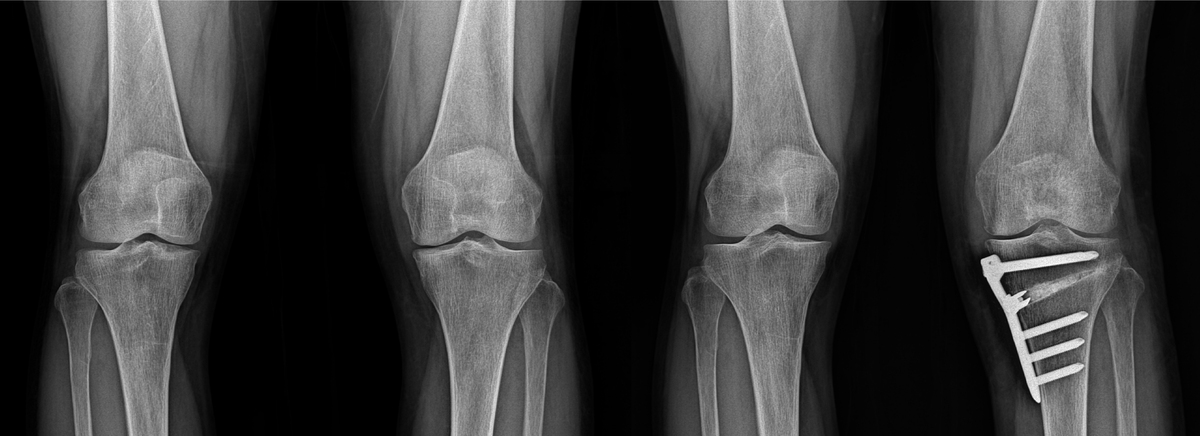

근위경골절골술은 무릎 아래 정강이뼈 윗부분을 일정 각도로 절개해 다리 축을 교정하고, 체중 부하를 건강한 외측 관절면으로 분산시키는 수술이다. 관절내시경으로 연골·연골판을 정리한 뒤 절골 부위를 벌려 뼈 이식을 하고, 금속판과 나사로 고정한다.

내측 관절염이 2~3기이고, 가쪽 관절과 인대가 비교적 보존된 젊은 환자에게 적합하다. 장점은 자기 관절을 보존해 운동 범위를 유지하고, 러닝·테니스 복귀가 가능하며, 관절염 진행 속도를 늦춰 인공관절 시기를 미룰 수 있다는 것이다.